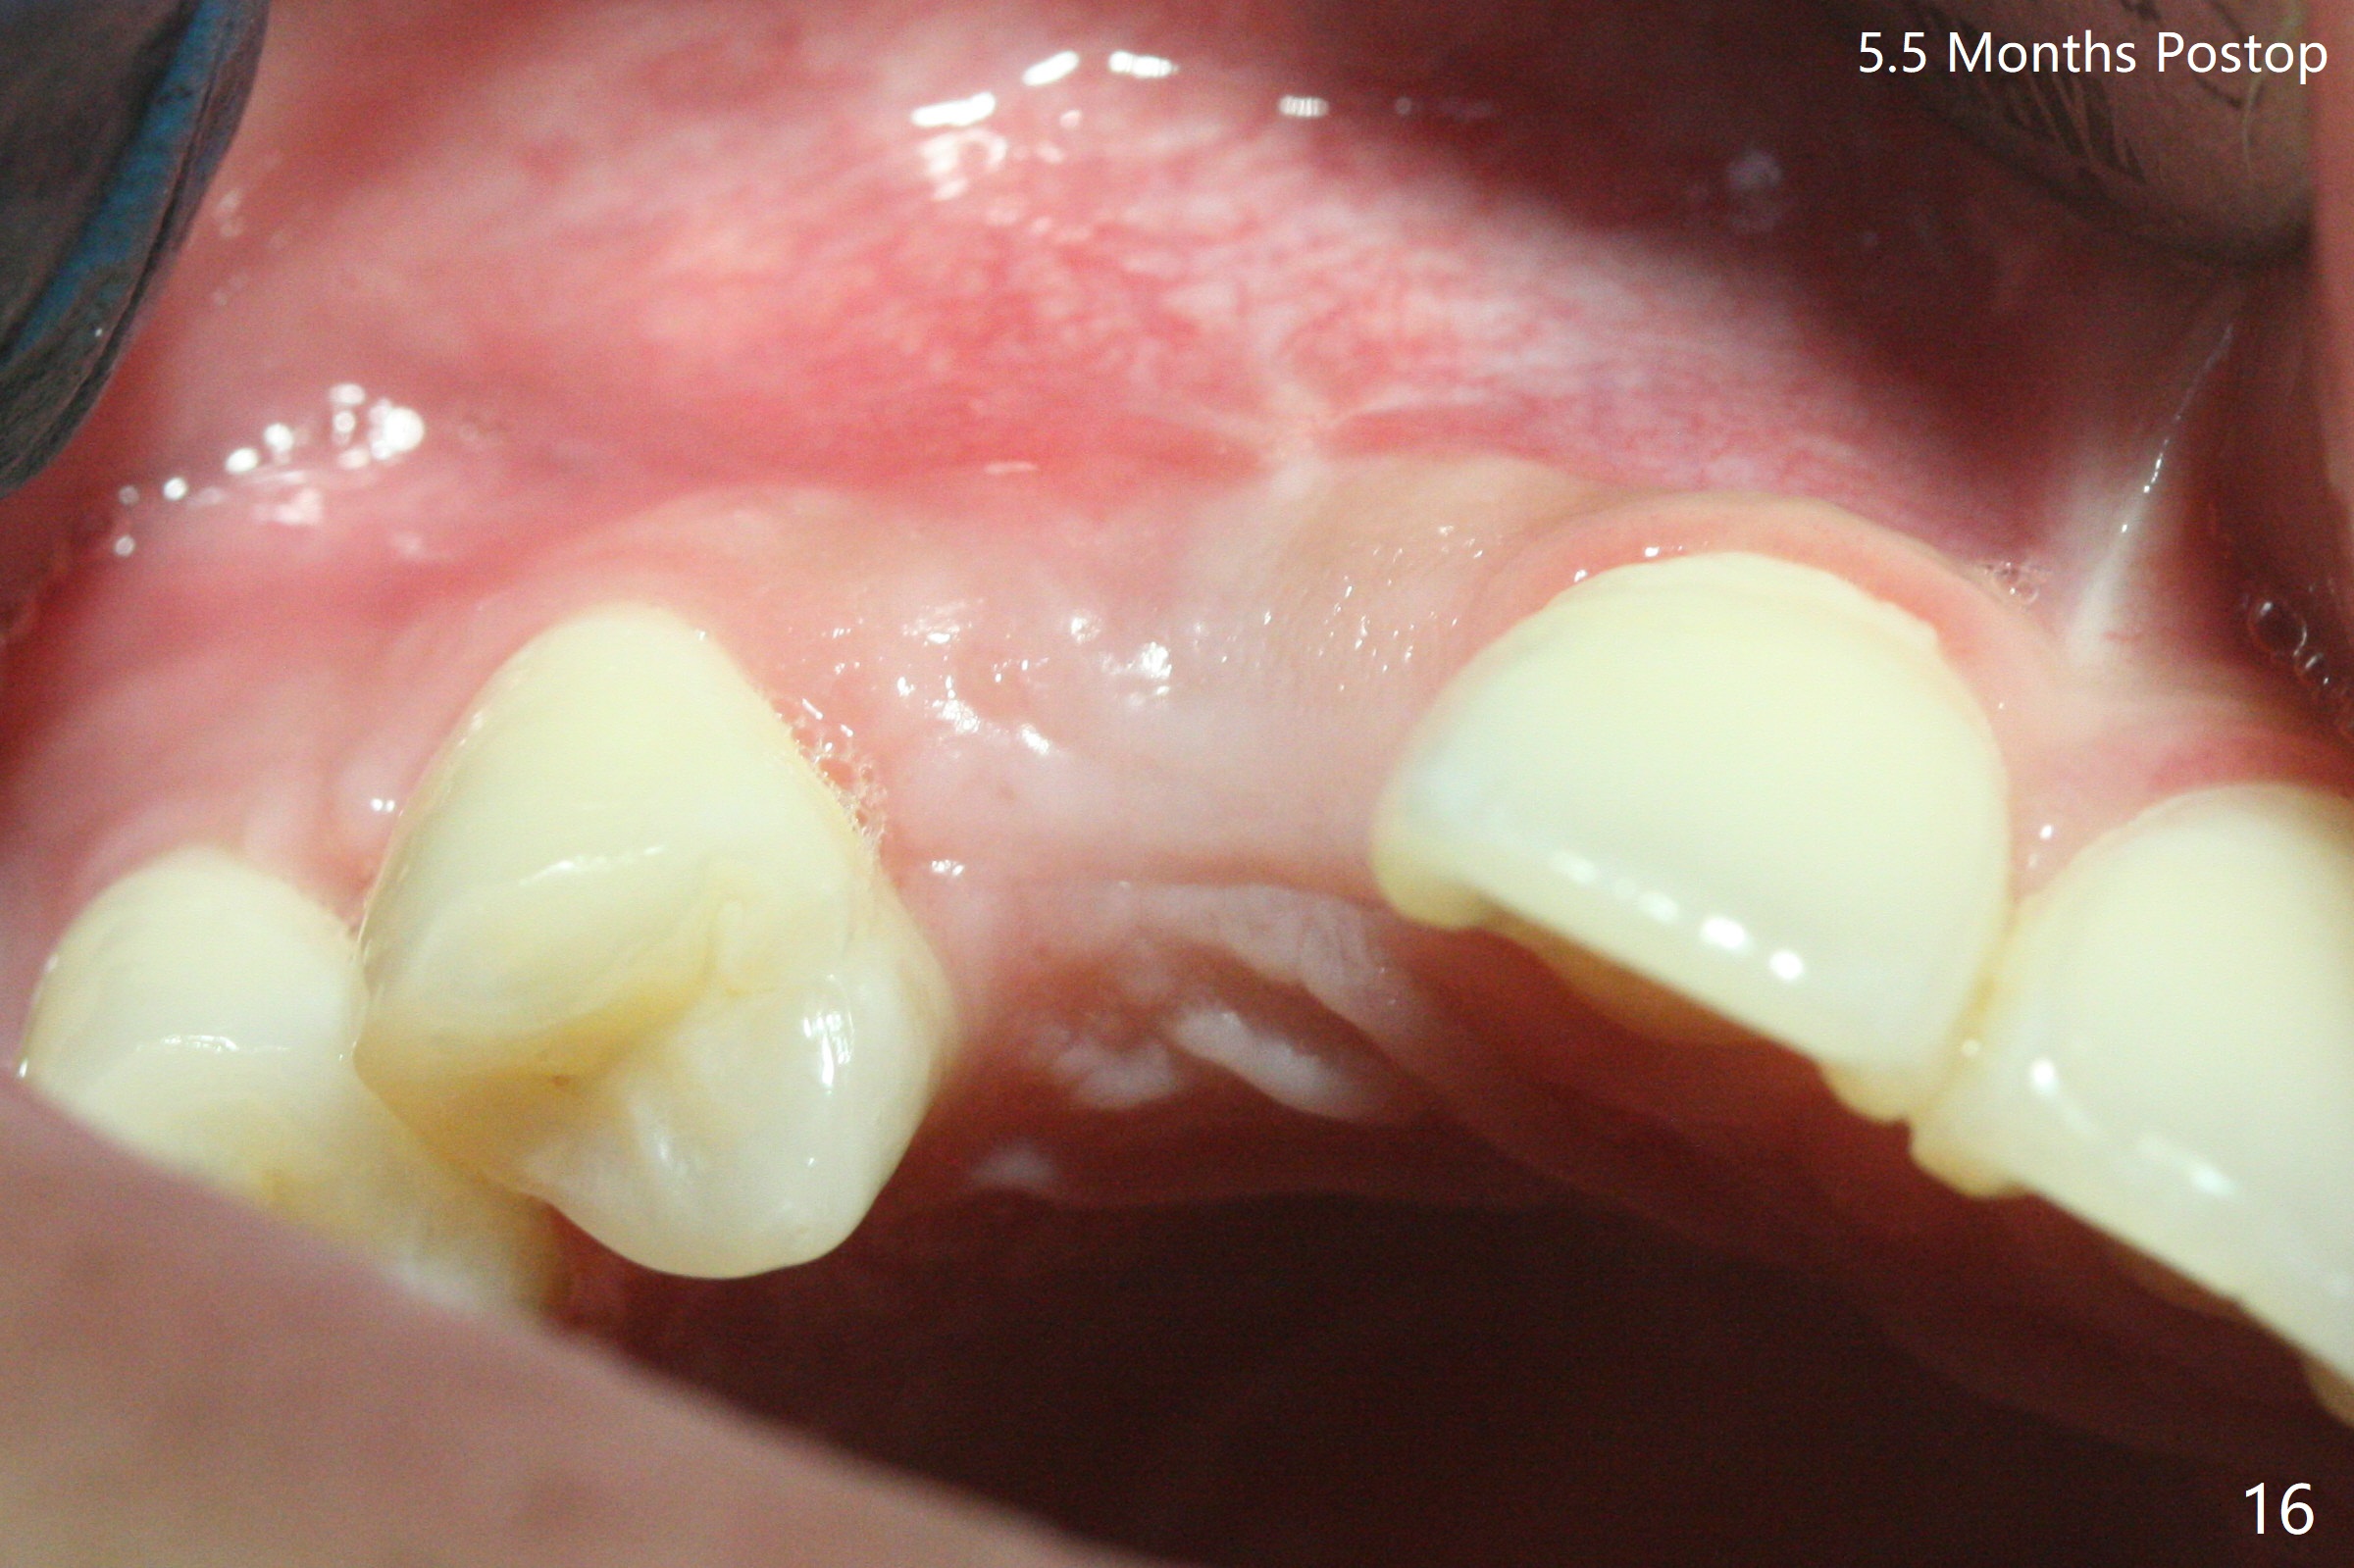

18岁男从外州大学回来,无症状,但是6号牙(右上尖牙)颊侧瘘道(图一,二(角化龈充分(箭头))),根尖片显示植体近中骨吸收(图三:*),而对侧植体仿佛骨整合(图四)。患侧切开后发现植体颊侧暴露,松动。拔除后骨缺损由粘性骨粉修复(图七,九:*),覆盖PRF膜(图七:P)和带钛网(图九:^)不可吸收膜(图五-七),后者用两个小钉子固定(图六(腭侧),七(颊侧),九),使用新的刀片和一个特殊尖头剥离器在颊侧骨膜下相当广泛分离,使用PTFE缝线,粘膜下水平褥式缝合之后(图八:箭头),多个垂直间断缝合,两个乳头垂直褥式缝合。术后一周伤口没有裂开,术后疼痛肿胀已经消退(图十)。术后十八天牙槽嵴仿佛比对侧还要宽(图十一,三与图十二,四(取模)对比)。术后5.5个月伤口没有裂开,牙槽骨,角化龈宽(图十六),与钛网和两个小钉子固定有关(图十五,十七)。CT显示牙槽骨只能容纳2.5或者3.0毫米植体(图十八)。11号牙植体牙冠粘固后没有骨质吸收(图十九),其实10,11号牙颊侧骨板隆起(图二十至二十二),而6植体失败,颊侧骨板吸收,甚至累及5号牙(图十七)。